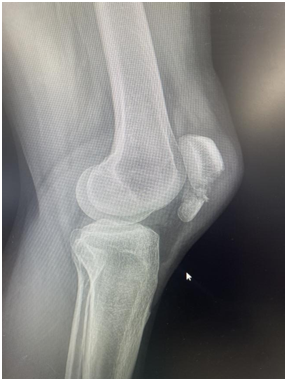

在西安高新医院骨科一病区经过检查后,医生诊断她的“髌骨”骨折了。什么是髌骨?它就是咱们常说的“膝盖盖”,你可以把它想象成膝盖前方的一块小盾牌,负责保护膝关节,并在我们伸直腿时发挥关键作用。文女士跪地的那一下,正好是这块“小盾牌”直接承受了全身的重量和撞击,导致它碎裂了。这种情况需要手术才能让碎骨块重新长好,恢复膝盖功能。

但与大家想象中“开大刀”的场景不同,西安高新医院骨科一病区杨鹏主任为她制定了一个微创手术方案。用小切口,解决大问题,杨鹏主任通过一个小切口,在X光机的“导航”下,将碎成几块的膝盖重新对拼好,然后用一套专门的内固定材料(通常是钢丝和钢钉)从内部将其牢牢固定住。这个手术的名字叫“左侧髌骨骨折闭合复位内固定术”。